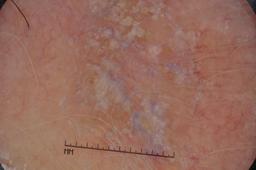

ISIC-DICM-17K (ISIC Dermoscopic Images and Clinical Metadata 17K) is a curated and balanced dataset derived from the International Skin Imaging Collaboration (ISIC) Archive Gallery. It comprises 17,060 dermoscopic images and clinical metadata (8,530 melanoma and 8,530 non-melanoma classes).

For more details, please follow the project’s GitHub repository: https://github.com/mmu-dermatology-research/isic-dicm-17k

This dataset was used in this study and benchmark to explore the effectiveness of multimodal learning for skin lesion classification:

S. Ahammed, X. Cui, W. Lu and M. H. Yap, "Skin Lesion Classification using Dermoscopic Images and Clinical Metadata: Insights from Multimodal Models," 2025 IEEE/CVF Conference on Computer Vision and Pattern Recognition Workshops (CVPRW), Nashville, TN, USA, 2025, pp. 222-230, DOI: 10.1109/CVPRW67362.2025.00027